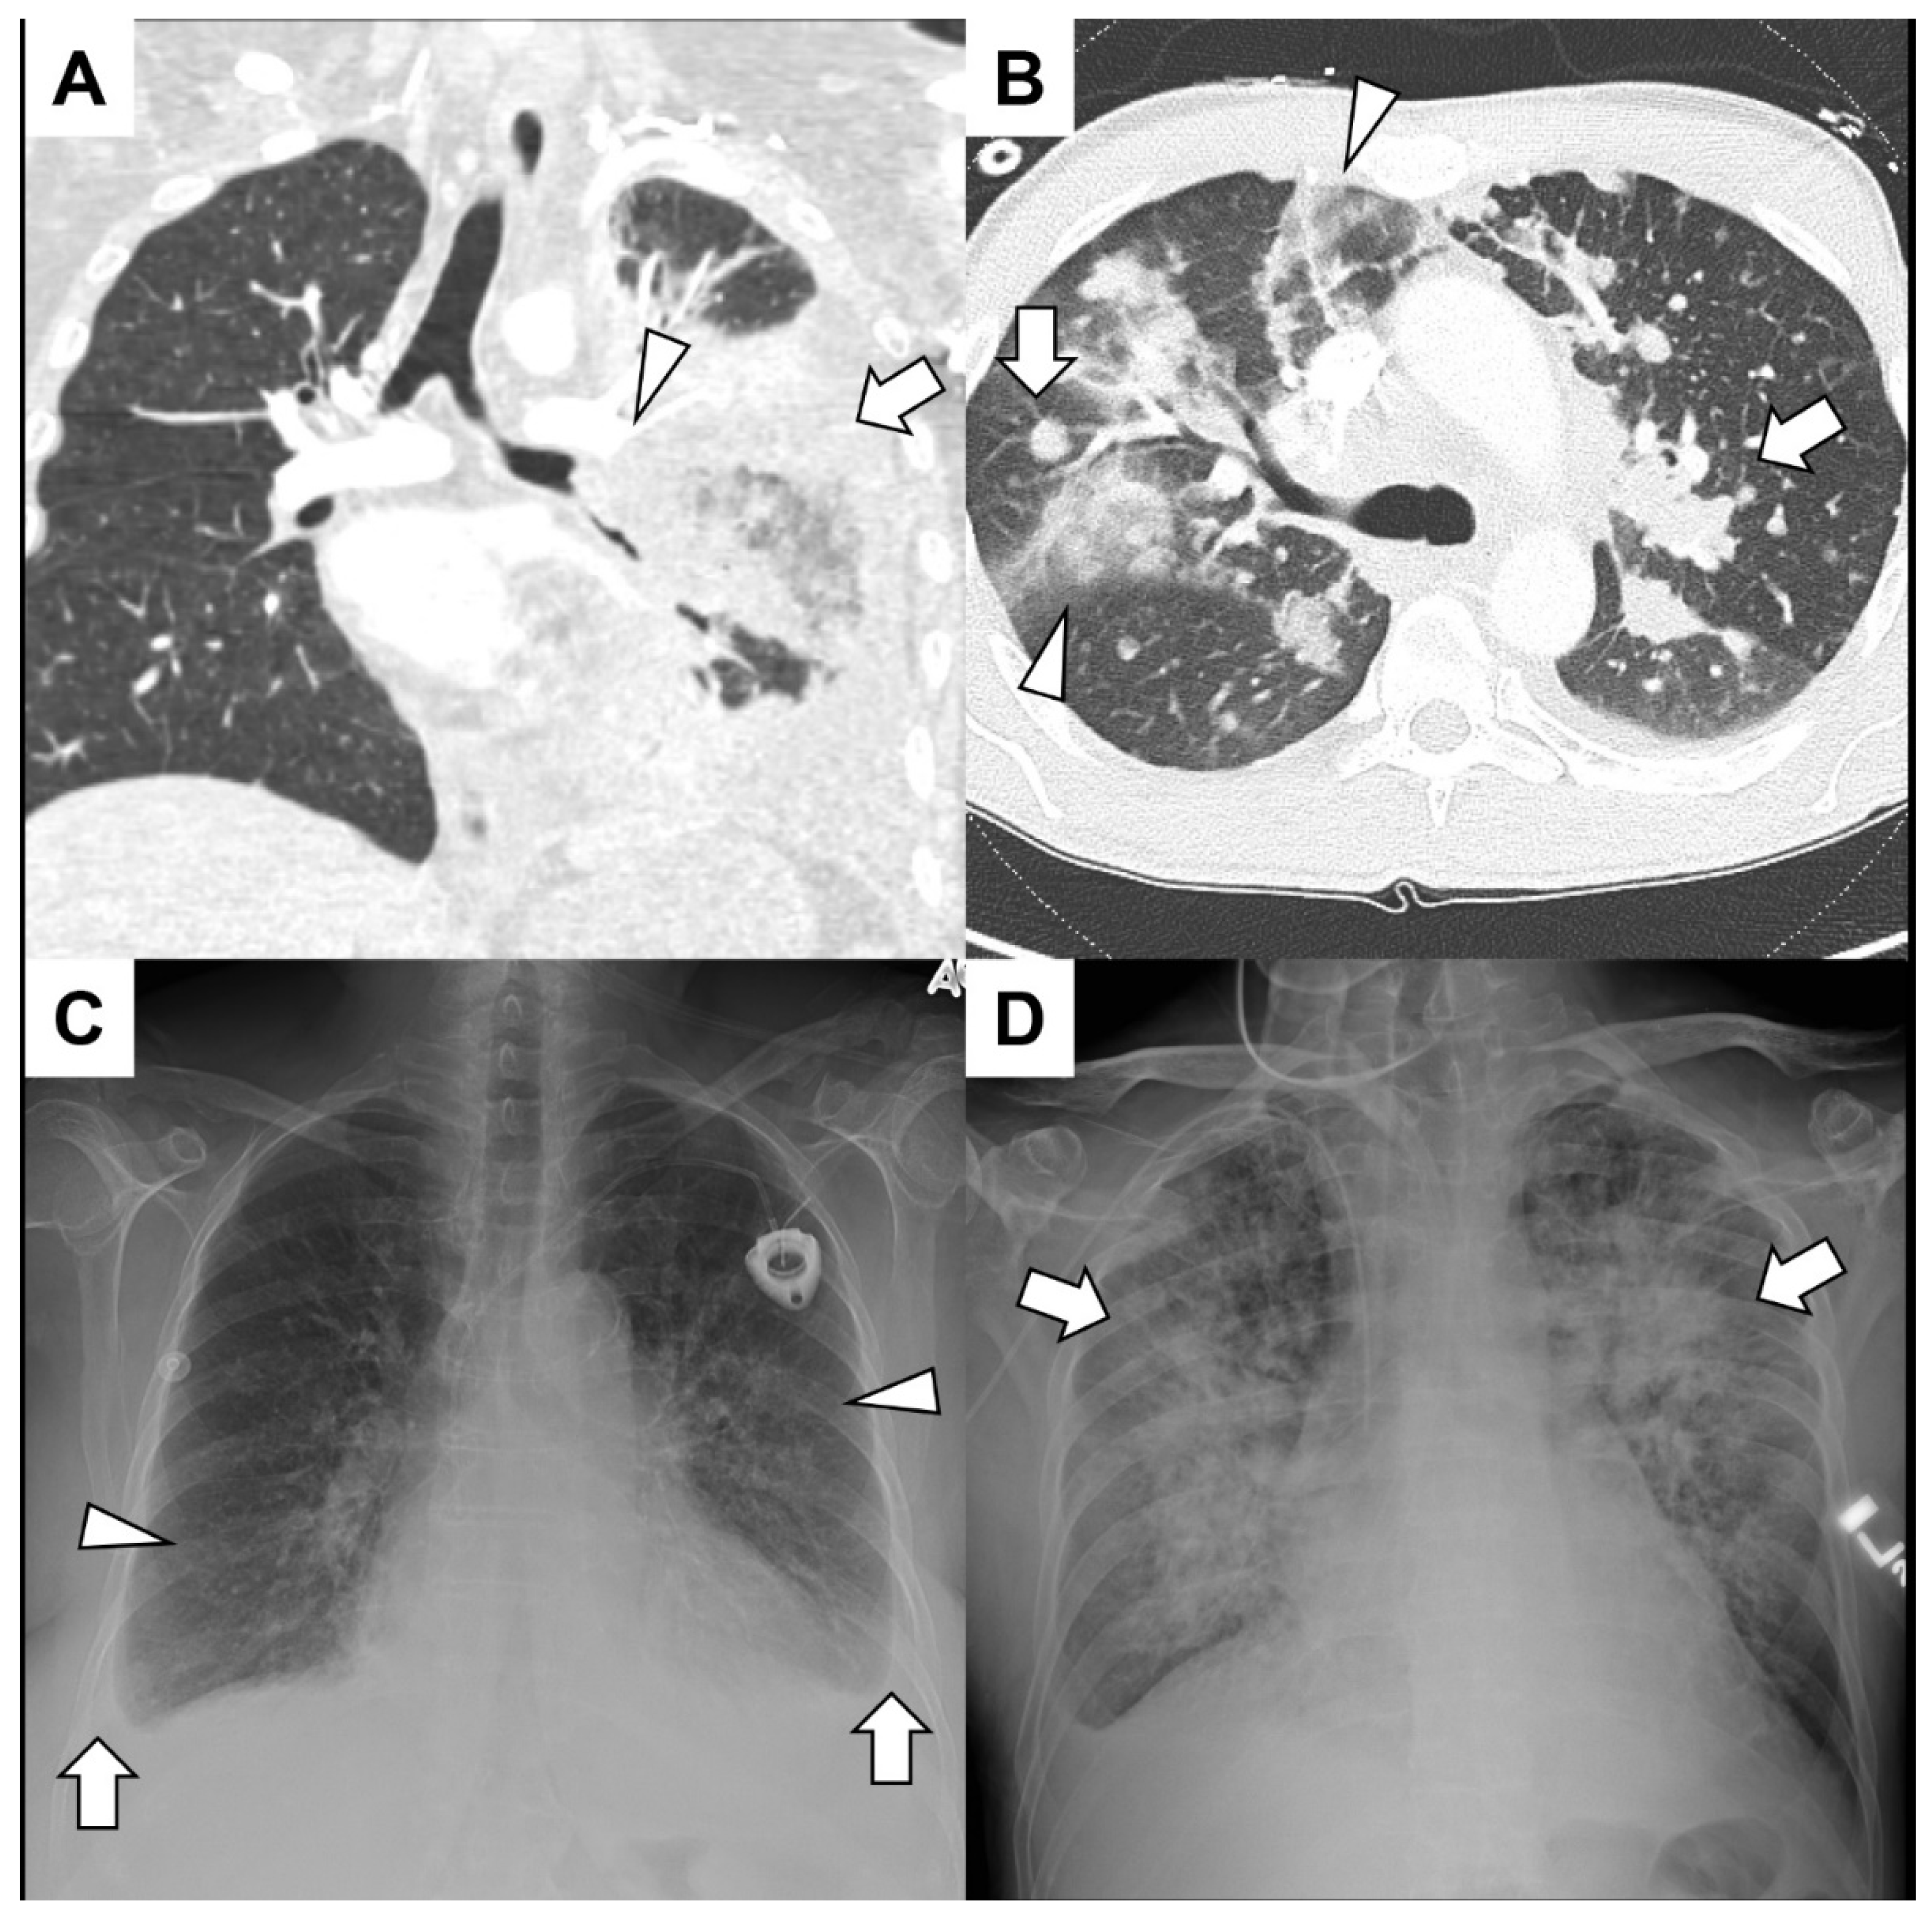

5.1. Primary Lung Cancer

5.2. Pulmonary Metastasis